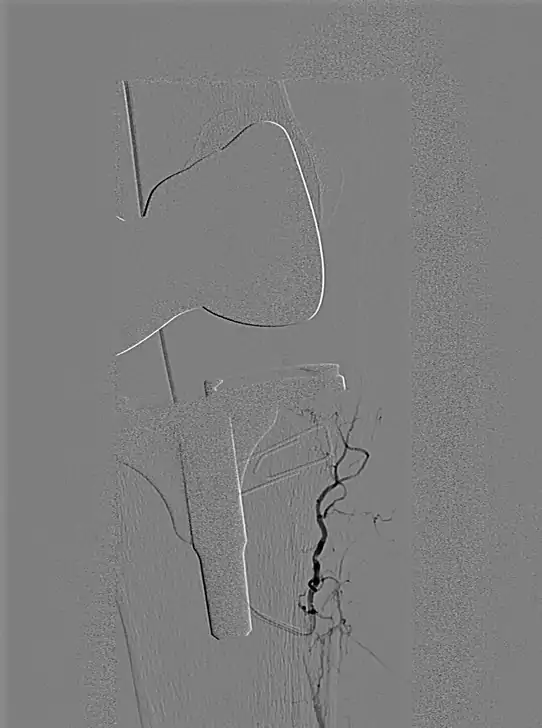

Innovativ ging es weiter mit Dr. Guido Zintl (Oberarzt der Radiologie am GK-Bonn). Er stellte die noch relativ junge operative TAPE-Therapie als neue Hoffnung für Arthrose-Patient:innen vor.

Bei Kniearthrose führen chronische Fehlbelastungen und Entzündungsreize häufig dazu, dass sich im Gelenk zusätzliche feine Blutgefäße und krankhafte Nervenfasern entwickeln, die Schmerzreize ans Gehirn übermitteln. Betroffene sprechen oft schlecht oder gar nicht auf Medikamente an, sodass diese nur begrenzt Linderung bringen.

Das schonende TAPE-Verfahren (Abkürzung für transarterielle periartikuläre Embolisation) bietet hier Hilfe: Durch den vorübergehenden Verschluss der überzähligen Gefäße werden Nervenschmerzen stark vermindert oder sogar gestoppt. Die gesetzlichen Krankenkassen übernehmen bei passender Indikation die Kosten für diese schonende Operation mittels Mikrokatheter.